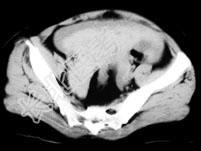

- 单项选择题女,32岁, 因停经46天,少许不规则阴道流血15天, 下腹胀痛3天入院,后穹窿穿刺抽出不凝血, CT检查如图所示,下列说法错误的是 ( )

A、在左附件区可见一椭圆形略高密度病灶

B、病灶外缘较光整

C、盆腔内较高密度积液

D、考虑为宫外孕

E、考虑为卵巢巧克力囊肿